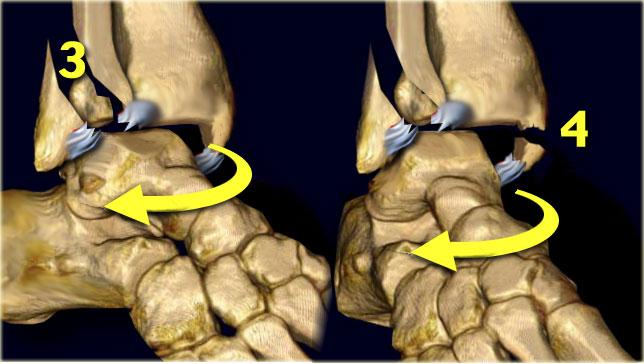

Stage 3-4

Giai đoạn 3 Sự dịch chuyển ra sau nhiều hơn của mảnh mắt cá ngoài do xương sên gây ra lực căng lên khớp chày mác sau dẫn đến đứt hoặc bong điểm bám của mắt cá sau.

Giai đoạn 4 Sự di chuyển ra sau thêm của xương sên sẽ gây ra căng thẳng cực độ ở phía trong và dây chằng delta sẽ hoặc bị đứt hoặc bị bứt ra khỏi mắt cá trong theo mặt phẳng ngang.

Các giai đoạn trong gãy xương Weber B hoặc tổn thương xoay ngoài-sấp theo phân loại Lauge-Hansen diễn ra theo chiều kim đồng hồ:

- Rupture of the anterior tibiofibular ligament

- Oblique fracture of the distal fibula

- Avulsion của mắt cá sau hoặc đứt dây chằng chày mác sau

- Avulsion của mắt cá trong hoặc đứt dây chằng bên trong

Ngay sau khi chấn thương, các phần bị tổn thương có thể tự sắp xếp lại vị trí, điều này có thể gây khó khăn trong việc phát hiện các tổn thương.

Stage 2-3

Xương sên xoay ra ngoài và di chuyển sang bên do không còn bị ràng buộc bởi phần bám vào phía trong.

Do sự sấp, các dây chằng bên ngoài không còn chịu lực căng và xương mác có thể di chuyển ra xa xương chày.

Điều này gây ra đứt khớp chày mác trước. Đây là giai đoạn 2.

Lực liên tục sẽ xoắn xương mác và di lệch nó về phía xa, trong khi ở phía gần nó được cố định vào xương chày.

Cuối cùng màng gian cốt sẽ rách đến điểm mà thân xương mác bị gãy. Đây là giai đoạn 3.

Vị trí này luôn ở trên mức của khớp chày mác xa.

Trong nhiều trường hợp có thể thấy trên phim X-quang cổ chân, nhưng trong một số trường hợp vị trí gãy xương nằm cao và chỉ có thể thấy trên phim X-quang cẳng chân.

Loại gãy xương sau này còn được gọi là gãy xương Maisonneuve.

Here we see the different stages in the axial plane.

- Medial avulsion fracture or rupture of the collateral band

- Rupture of the anterior syndesmosis

- Suprasyndesmotic rupture of the fibula due to rotation

- Gãy mắt cá sau hoặc đứt dây chằng chày mác sau